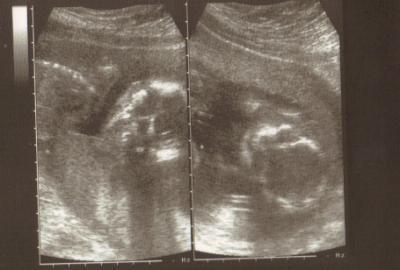

Und der kleinere 20 cm un 280 g

Bild zu

Ach wie schön *schwärm* Für Zwillis sind die Jungs aber gut im Wachstum. Völlig normal. Freut mich sehr für euch. GLG Claudia